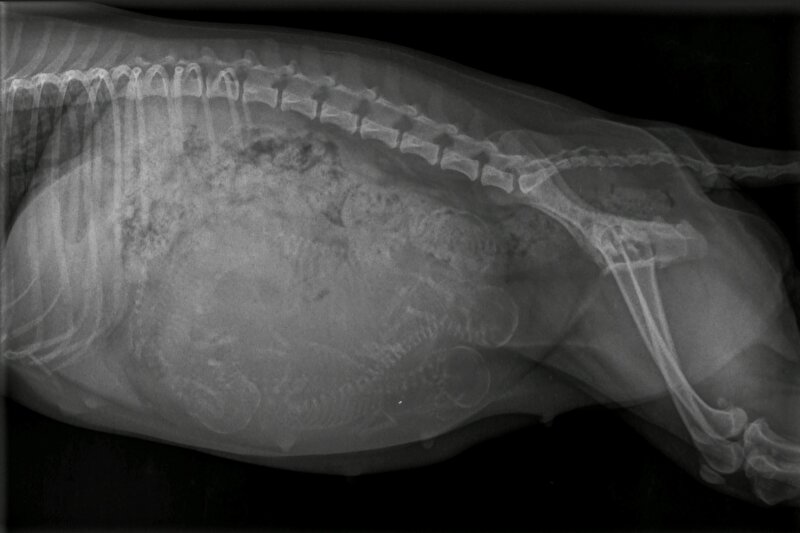

Het kan ook wel. Maar de ervaring is dat je dan gewoon een slecht beeld hebt. Als je wacht tot 55+ dagen zie je het veel duidelijker. En daar doe je t voor..

En altijd van 2 zijkanten foto’s maken. Soms liggen pups wat verstopt en dan zie je ze vanaf de ene kant niet liggen.

En de reden dat ik daar over “zeur” is dat de baarmoeder een vorm van een Y heeft. Dat wil zeggen: 1 baarmoederhoorn linkerzijde hond en 1 rechterzijde. Op de eerste foto lijkt een 5e aanwezig, die op de 2e foto bijna niet meer te zien is. Wat kan betekenen dat er nog steeds een nr 5(of6) aanwezig is, want wat je ook op de foto ziet is een gevulde darm. Ter hoogte van de 3 schedels is het dus te vol van ontlasting om een goed beeld te krijgen.

Maar vooraan vind ik het beeld ook te vaag om duidelijk te zien wat daar zit. Ik zou dus zeker nieuwe foto’s maken en dan van beide kanten.

Het zijn in ieder geval minimaal 4 pups, maar het zou me niets verbazen als er straks nog meer uitkomen.

floorsil schreef:Volg gewoon even mee.maar als ik hoofdjes of ruggengraten tel ik er 6 . Hoe zit dat? Heel veel succes met de laatste loodjes.